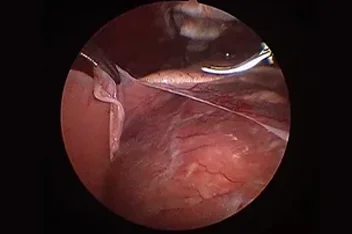

흉강경

복강경과 유사하게 최소 절개를 통해 흉강 수술을 진행하게 됩니다.

작은 구멍으로 카메라 포트가 진입하여 수술 부위를 시각화하고 진단과 치료를 진행할 수 있습니다.

흉강에서는 탐색과 조직생검을 통해 확실한 진단에 도움이 됩니다.

심낭수 치료를 위해 심낭막절제술, 최소침습 폐엽절제, 유미흉의 치료를 위한 흉관결찰(Thoracic duct ligation) 등이 진행될 수 있습니다.

흉강경심막절제술 (Preicardiectomy)

흉강경흉관결찰 (Thoracic duct ligation)